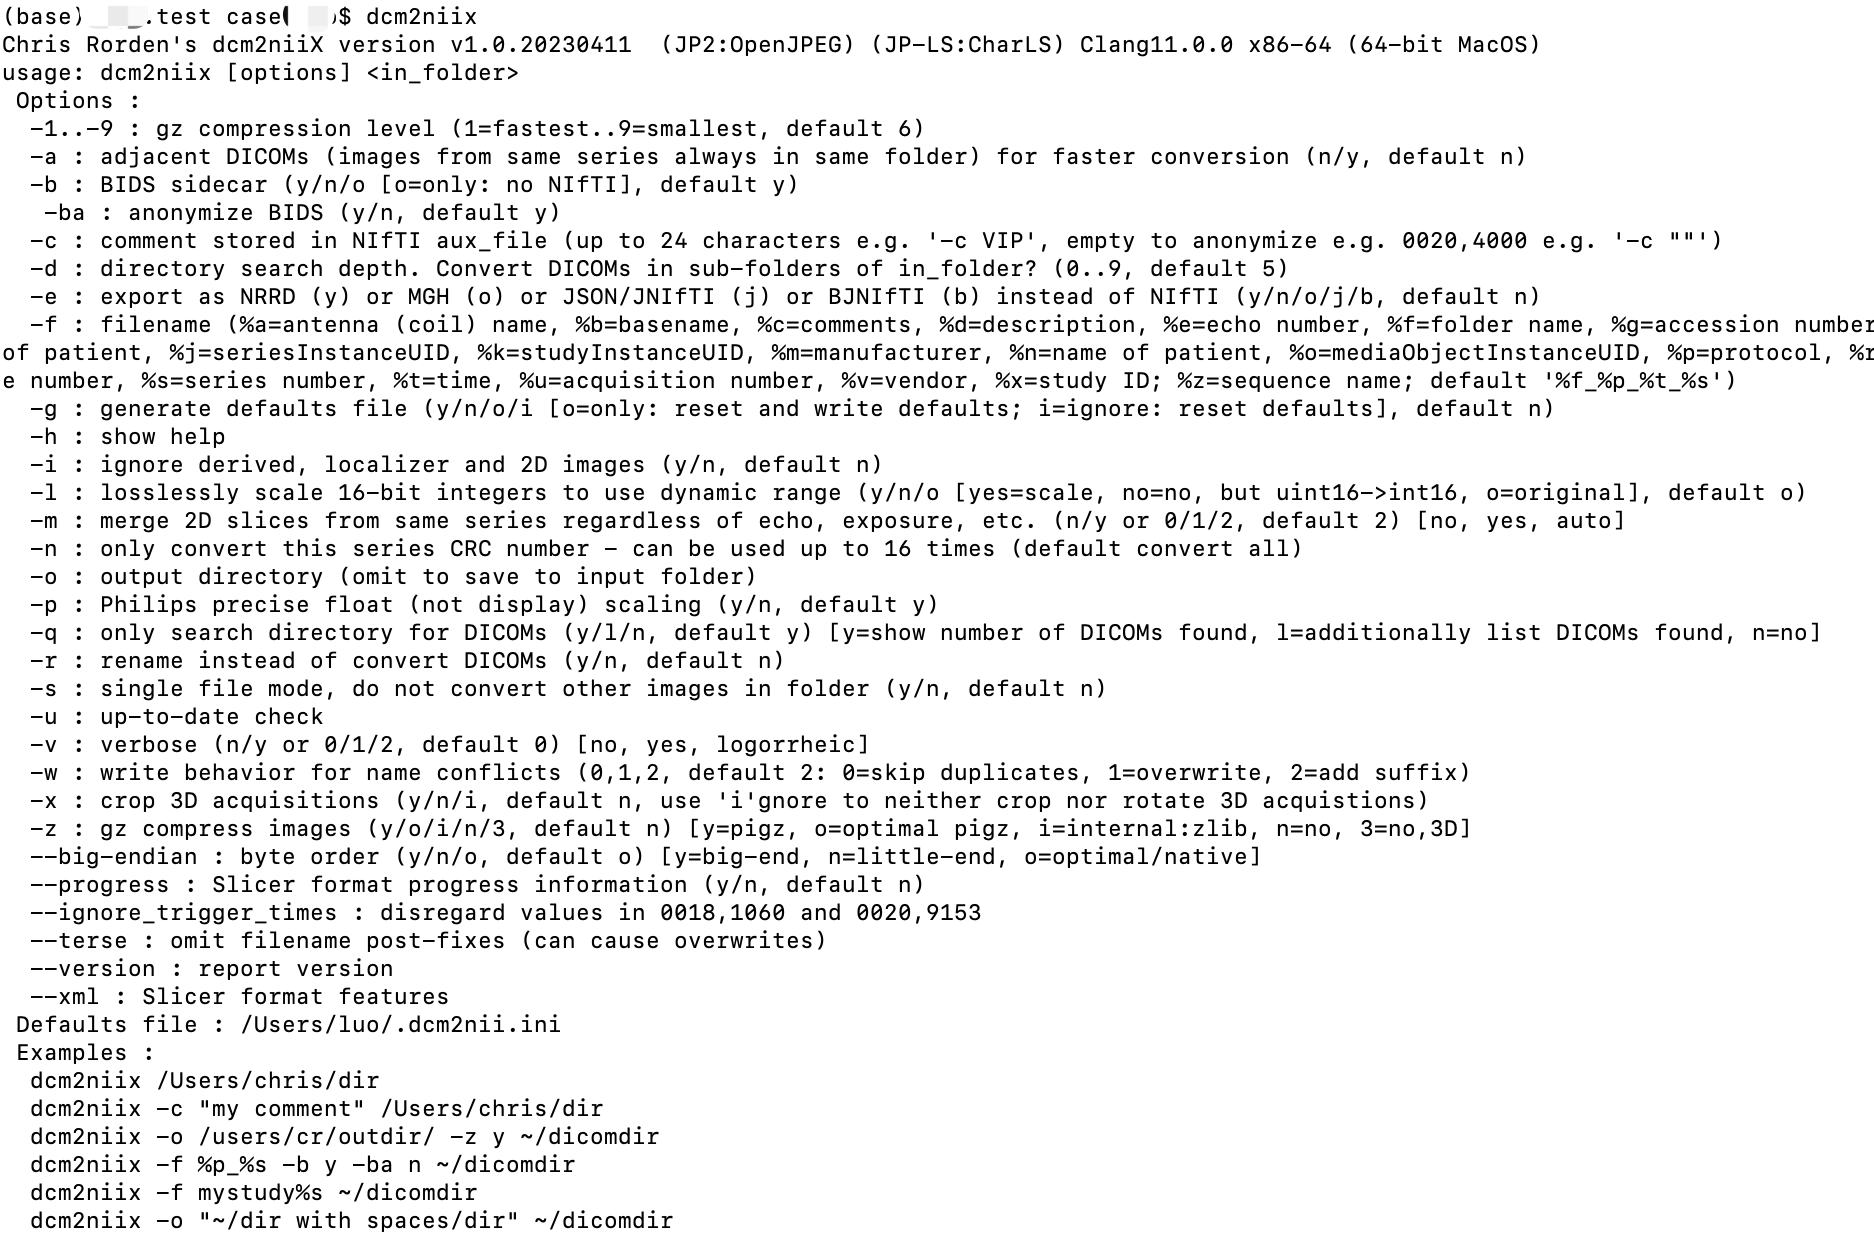

dcm2niix 命令行详细使用说明

dcm2niix 命令中唯一必填的参数是:需要转换的 DICOM 文件夹的位置,该参数始终作为最后一个参数进行提供。例如,dcm2niix ~/dicomdir 将会转换文件夹 “dicomdir” 中的所有 DICOM 文件。但是,你可以指定一些可选参数来影响转换结果。

因此,一个典型的转换命令可能是 dcm2niix -o ~/niftidir -f %p_%s -g y ~/dicomdir。

在这个例子中,软件会在 dicomdir 中查找 DICOM 图像并将转换后的 NIfTI 文件保存在 niftidir 中,输出文件将被压缩,并包含协议名称 (%p) 和序列号 (%s) 作为文件名。

下面是详细的参数列表(在终端直接输入 dcm2niix 命令来查看所有命令的列表)。以下是各个参数的说明:

- -1…-9 压缩级别(1为最快,9为最慢但会产生更小的文件,默认为6)。

- -b: BIDS sidecar:(“-b y”或“-b n”, 默认为 y)如果选择“yes”,则软件将生成与NIfTI图像同名的一种Brain Imaging Data Structure文件。该文件采用JSON文本格式,提供了有关扫描的附加信息,这些信息无法保存在NIfTI头文件中

-baBIDS sidecar的匿名化:(“-ba y”或“-ba n”)如果选择“no”,则BIDS文件将包含编码在DICOM文件中的参与者个人信息。这些识别信息可能会危及参与者的隐私。此选项仅影响BIDS sidecar(见b)。

- -f 输出文件名:(例如“-f myMR”, 默认 ‘%f_%p_%t_%s’)dcm2niix允许您指定转换后的 NIfTI 文件的命名方式。该方法可能一开始看起来很复杂,但它提供了非常大的灵活性。

一个简单的文件名可能是“exp03subj09”。

在这种情况下,这个参与者的第一个序列将被命名为exp03subj09.nii,

接下来是exp03subj09a.nii,然后是exp03subj09b.nii等等。

但是

dcm2niix还允许您将相关信息的存在和位置标注到文件名中。

考虑您指定“exp03subj09%p%s”

在这种情况下,协议的名称和序列号(存储在DICOM文件中)将成为文件名的一部分。

在这种情况下,输出文件的名称可能是exp03subj09fmri1.nii、

exp03subj09t12.nii

和exp03subj09fmri3.nii。

您可以按任意顺序组合尽可能多的修饰符。

以下是特殊修饰符的列表:

%a:插入天线(线圈)编号。例如,“myName%a”的输出文件名将生成“myName1”,“myName2”等,每个线圈一个。请注意,大多数扫描都会将所有线圈的数据组合在一起,在这些情况下,该选项将被忽略。例如,大多数将所有线圈的数据组合在一起的扫描通常只称为“myName”。

%d:插入系列描述(0008,103E)。例如,使用“myName%d”转换的回波平面图像会产生“myNameEPI”

%e:插入回波数。例如,具有两个回波时间的序列使用输出文件名“myName%e”进行转换,将产生“myName1”和“myName2”。请注意,大多数MRI序列仅使用单个回波时间,在这种情况下,您只会得到“myName1”。

%f:插入输入文件夹名。例如,使用输入文件夹“/usr/Subj22”和输出文件名“myName%f”将导致输出文件命名为“myNameSubj22.nii”。

%i:插入病人ID(DICOM标签0010,0020)。例如,“myName%i”的输出文件名将把病人ID命名为“ID123”的图像转换为“myNameID123.nii”

%m:制造商名称。 例如,“myName%m”的输出文件名将把来自GE扫描仪的图像转换为“myNameGE.nii”,而来自Philips的图像将变为“myNamePh.nii”,而Siemens将变为“myNameSi.nii”,否则制造商不可用(“myNameNA.nii”)。 (需要2015年或之后的dcm2nii版本)。

%n:插入受试者姓名(DICOM标签0010,0010)。例如,“myName%n”的输出文件名将把来自John Doe的图像转换为“myNameJohnDoe.nii”。如果您的参与者名称仅使用英文字母,则此选项最有效。对于其他欧洲语言,您可能会发现它进行一些基本转换(“Müller”将变成“Muller”)。对于非欧洲语言,您会发现此选项不满意。也许以后的版本可以支持DICOM标签0008,0005。

%p:插入协议名称(DICOM标签0018,1030)。例如,“myName%p”的输出文件名将把协议命名为T1的图像转换为“myNameT1.nii”

%q:插入序列名称(DICOM标签0018,1020)。例如,使用输出文件名“myName%q”将旋转回波序列转换为“myNameSE.nii”(新功能,在2015年8月30日版本中)。

%s:插入系列(DICOM标签0020,0011)。例如,使用输出文件名“myName%s”将第二个序列转换为“myName2.nii”。如果您想将系列号补零,请插入所需的数字数(0..9)。例如,在转换11个序列时应用过滤器“m%s”将创建文件,这些文件将导致简单的按字母排序出现问题,例如“m1.nii,m11.nii,m2.nii...m9.nii”的区别在于指定“m%3s”将有助于排序(例如“m001.nii,m002.nii...m011.nii”)。

%t:插入会话日期和时间(DICOM标签0008,0021和0008,0030)。例如,“myName%t”的输出文件名将把会话开始于2014年1月13日下午1:23的图像转换为“myName20140113132322.nii”

%z:插入序列名称(0018,0024),因此使用“myName%z”转换的T1扫描可能会产生“myNameT1”。

- -h 显示帮助屏幕

- -m: 合并2D切片:(n/y or 0/1/2, default 2) [no, yes, auto])如果选择,同一系列的图像将堆叠到单个NIfTI图像中. 默认就好了,3维数据直接在同一个 nii 里面。

- -o: 输出文件夹(不给,就会直接放在input folder)

- -z: 是否压缩,(y/o/i/n/3, default n) [y=pigz, o=optimal pigz, i=internal:zlib, n=no, 3=no,3D] 一般会选择压缩(-z y)